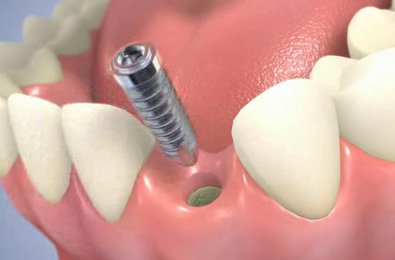

Diş İmplantları, eksik olan dişlerin yerine, çene kemiğine yerleştirilen titanyumdan yapılmış vidalardır. İmplantlar, küçük bir cerrahi işlemle çene kemiğine yerleştirilir. Bu işlemden sonra üç ay gibi kısa bir sürede tamamen çene kemiğine tutunur. Bu tutunma sonrası implant gerçek bir diş kökünün yerini alarak üzerine yapılacak protezi taşımaya hazır hale gelir.

Çene kemiğinin yeterli kalınlıkta ve yükseklikte olduğu durumlarda implant hemen yapılabilir. Çene kemiğinin yeterli olmadığı durumlarda ise bu bölgeye çeşitli işlemler uygulanarak kemik implanta uygun hale getirilir. Hastaların operasyon sonrası ağız hijyenine dikkat etmeleri gerekmektedir.